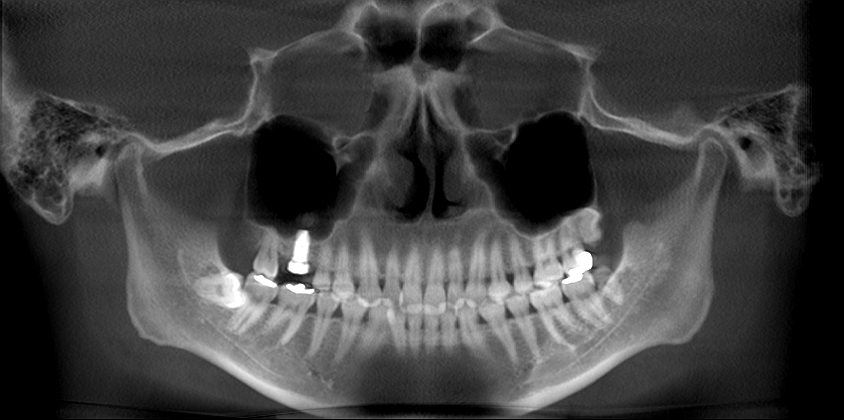

術前術後のパノラマになります

術前術後のパノラマになります